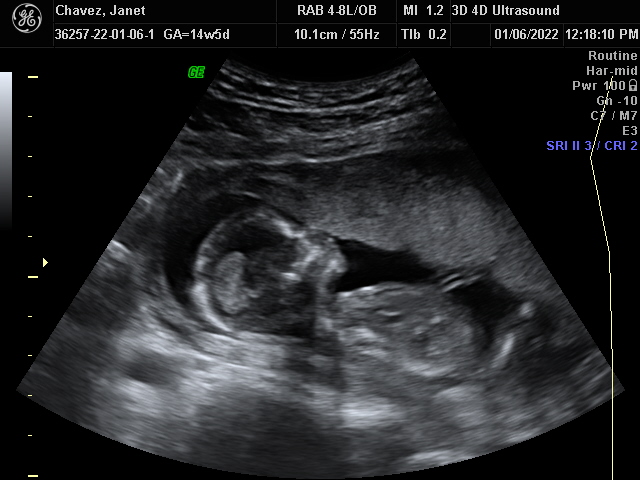

Our Gallery

Explore beautiful moments captured during our 3D and 4D sessions.